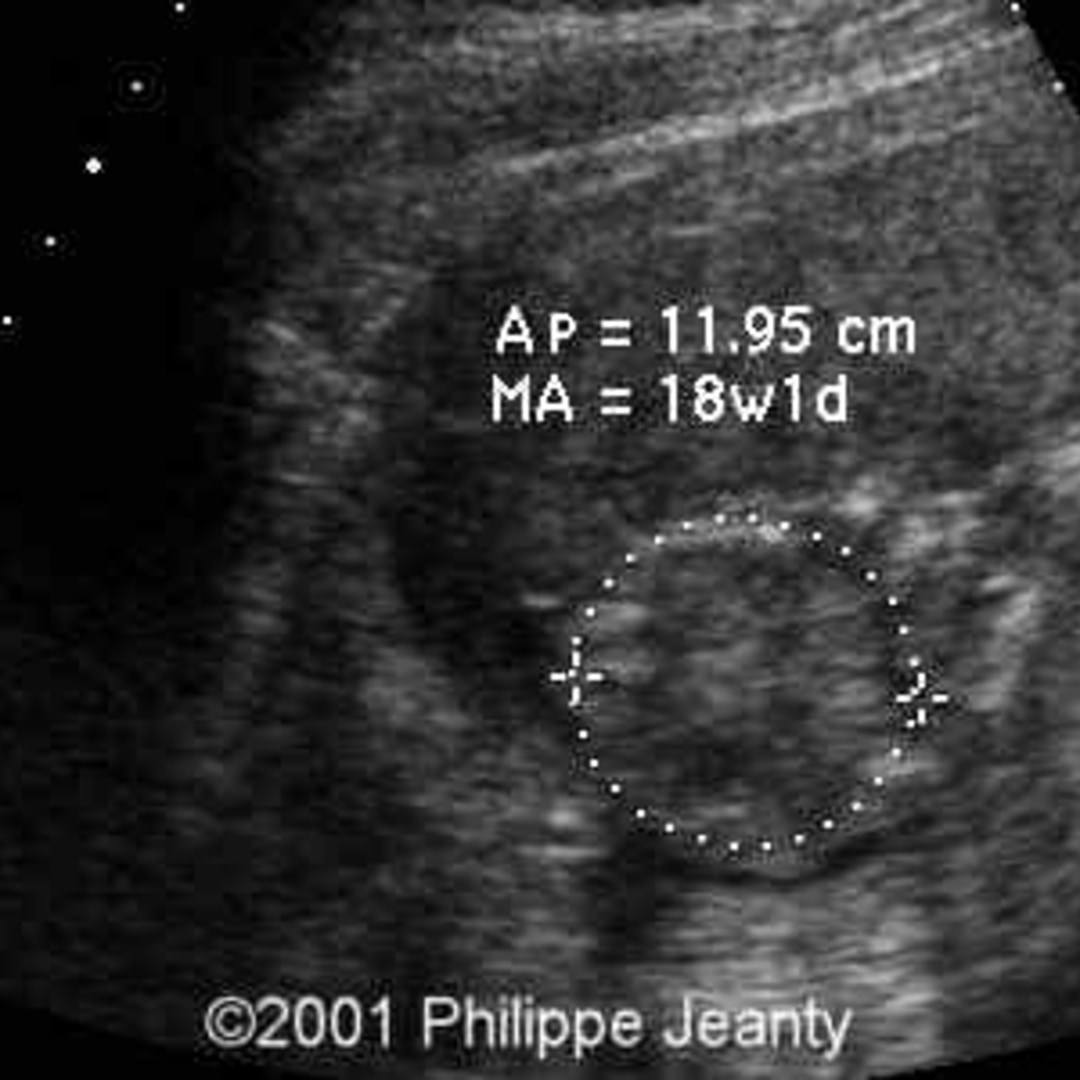

During pregnancy, women can be screened by chorionic villus sampling and amniocentesis to detect trisomy 16. With the advent of noninvasive techniques for detecting aneuploidy, prenatal screening with tests using Next Generation Sequencing can be utilised before invasive techniques. This can cause fetal growth retardation.

Mosaic trisomy 16, a rare chromosomal disorder, is compatible with life, therefore a baby can be born alive. This happens when only some of the cells in the body contain the extra copy of chromosome 16. Some of the consequences include slow growth before birth.

During prenatal diagnosis, the levels of trisomy in fetal-placental tissues can be analyzed. These levels can be predictors of outcomes in mosaic trisomy 16 pregnancies. In a study of prenatal diagnosis cases, there were 66% of live births with an average of 35.7 weeks gestational age. About 45% of them had malformations. The most common malformations were CSD, ASD, and hypospadias. However, confined placental trisomy 16 does not always result in anatomical abnormalities.